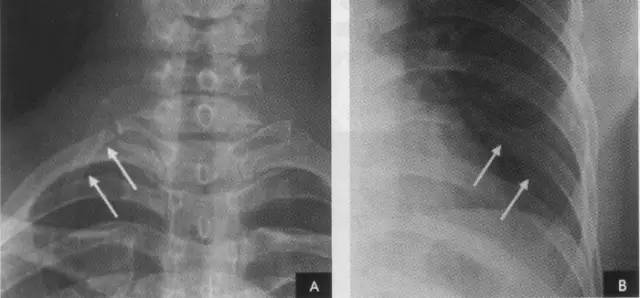

由于胸膜极为菲薄,x线检查时一般不能看到,只有在胸膜转折处,且x线与其走行方向平行时,才能在x线片上显示。以下几处正常胸膜可以显影: (一)肺尖部胸膜转折(第1、2肋骨伴随阴影)在正位胸片上,于肺尖部沿第1、2肋骨的下缘可见1~2mm宽的线条状阴影,边缘光滑,称为伴随阴影。

系胸膜在肺尖部的转折处以及胸膜外的一些组织的投影。

2、横裂又称水平裂,约70%的人正、撼位胸片均可显影。在正位片上表现为右中肺野横行细线状阴影,从第6肋腋部水平自外向内延伸.并止于肺门外lcm处。可向上或向下倾斜10:左右或略成曲线;在侧位片上,横裂起白斜裂中部,向前呈水平方向走行达前胸壁。其位置的改变可作为判断肺体积变化的标志(如上图)。